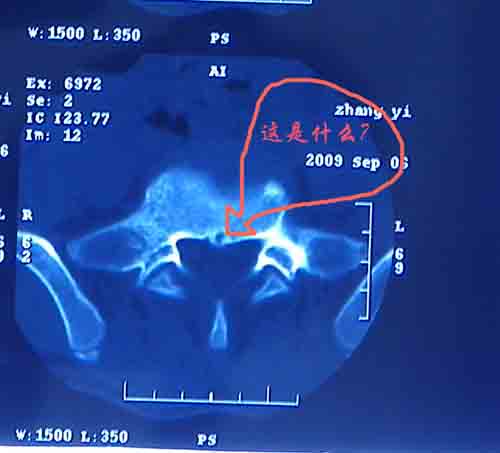

腰5/骶1椎间膨突出外,还有点异常,不知是什么东东,请各位大虾帮忙看看(12骨窗最明显)

椎体后缘软骨结节

软骨结节

支持 椎体后缘软骨结节。

支持椎体后缘软骨结节。